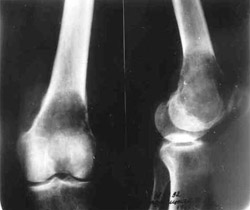

Tumour of lower/third of thigh-bone

Tumour of lower/third of thigh-bone.

Removal of tumour.

Replacement of hip defect.

In the making of replacement.

Results of treatment.